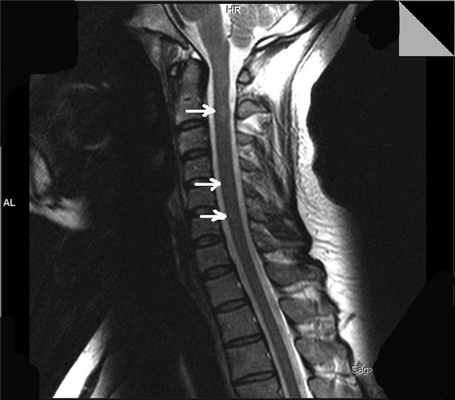

На уровне сегмента С2 определялись 2 интрамедуллярных очага без четких контуров, слабогиперинтенсивные на Т2-ВИ и изоинтенсивные на Т1-ВИ, размерами 4×6 и 4×7 мм. Не исключалось наличие аналогичного очага на уровне сегментов С4-С5 и С5-С6 шейного отдела спинного мозга (рис. 2). Рисунок 2. МРТ спинного мозга. На уровне сегмента С2 определяется 2 интрамедуллярных очага без четких контуров, слабо гиперинтенсивные на Т2-ВИ; не исключается наличие аналогичных очагов на уровне сегментов С4-С5 и С5-С6 шейного отдела спинного мозга (указано стрелками).

В большинстве случаев ССМ являются симптоматическими, и в их основе лежат очаги в спинном мозге, обусловленные каким-либо первичным заболеванием - инфекцией 26, опухолью [27], артериовенозной мальформацией [28], сирингомиелией [16], острым рассеянным энцефаломиелитом [29], вертебральной патологией [28], ятрогенией [125] и т.д. [10, 30-35]. Напомним, что у наблюдаемого больного обнаруживались очаги демиелинизации на уровне сегментов С2, С4, С5, С6 шейного отдела спинного мозга, и именно эти очаги могли служить причиной возникновения миоклонических подергиваний сегментарного характера (см. рис. 2).